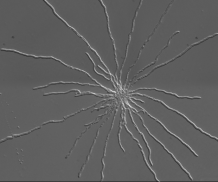

Microscopy image of Aspergillus fumigatus spores growing in liquid suspension.